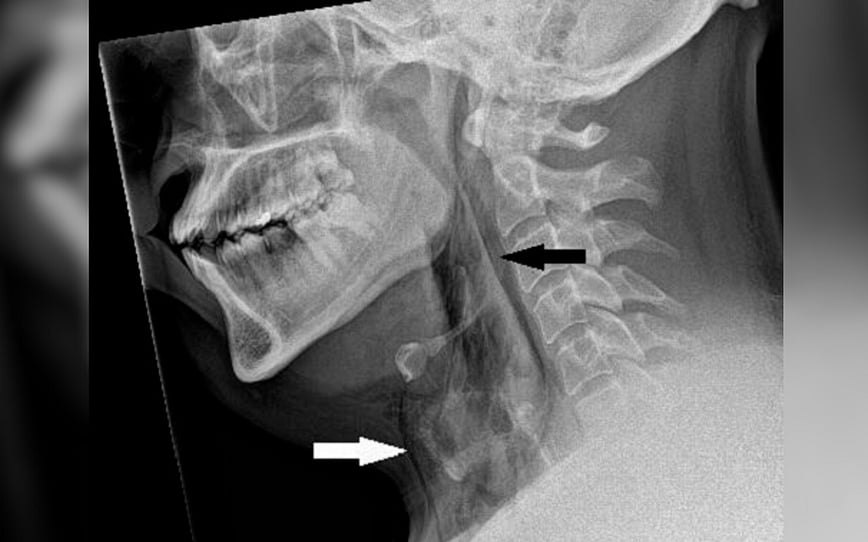

கழுத்துப் பகுதியில் வீக்கம் மற்றும் வலியுடன் மருத்துவரிடம் சென்றார் அவர். மருத்துவர்கள், அவர் கழுத்தின் இருபுறத்திலும் வீக்கம் இருந்ததைக் கண்டனர். இருப்பினும் அந்த நபருக்கு மூச்சுவிடவோ, பேசவோ, விழுங்கவோ எந்தப் பிரச்னையும் இல்லை. கழுத்தின் வீக்கத்தை பரிசோதித்தபோது அந்தப் பகுதியில் மெல்லிய சத்தம் வருவதை கவனித்தனர்.

பரிசோதித்தபோது அவரது மூச்சுக்குழாய் சேதமடைந்திருந்தது தெரியவந்தது. காரில் செல்லும்போது அவர் தும்மலை அடக்கியதால் அளவுக்கு அதிகமான அழுத்தம் மூச்சுப்பாதையில் ஏற்பட்டு, இயல்பான வேகத்தைவிட 20 மடங்கு கடுமையான தும்மல் ஏற்பட்டுள்ளது. அந்த அழுத்தம் மூச்சுக்குழாயில் 2 க்கு 2 மில்லி மீட்டர் அளவுள்ள துளையை ஏற்படுத்தியது. அதாவது மூச்சுப்பாதை கிழிந்து சேதமடைந்துள்ளது.